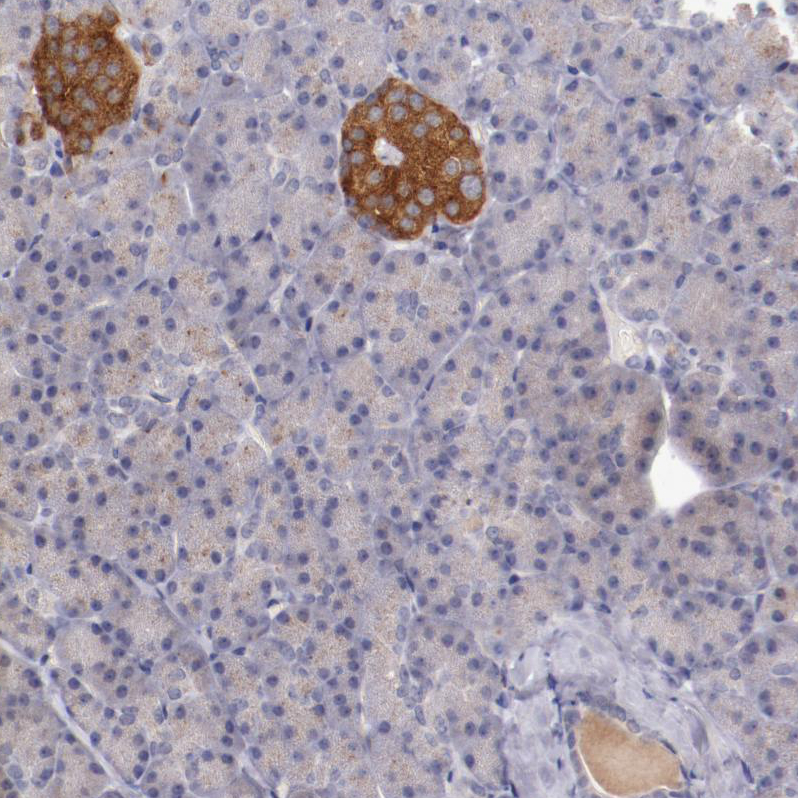

Immunohistochemistry analysis in human cerebral cortex and liver tissues using HPA002858 antibody. Corresponding SYP RNA-seq data are presented for the same tissues.